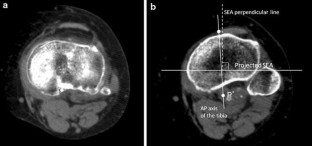

Preoperative computed tomography scans on 25 varus and 25 valgus knees undergoing TKA were studied. The SEA and the AP axis of the tibia were identified using a three-dimensional software, and the angle between the line perpendicular to the projected SEA and the AP axis was measured.

The AP axis of the tibia was 1.7° ± 4.3° and 2.0° ± 4.0° internally rotated relative to the line perpendicular to the SEA in the varus and valgus groups, respectively.

The AP axis of the tibia was, on average, perpendicular to the SEA in both varus and valgus knees. The AP axis would be useful for setting the tibial component with minimal rotational mismatch.